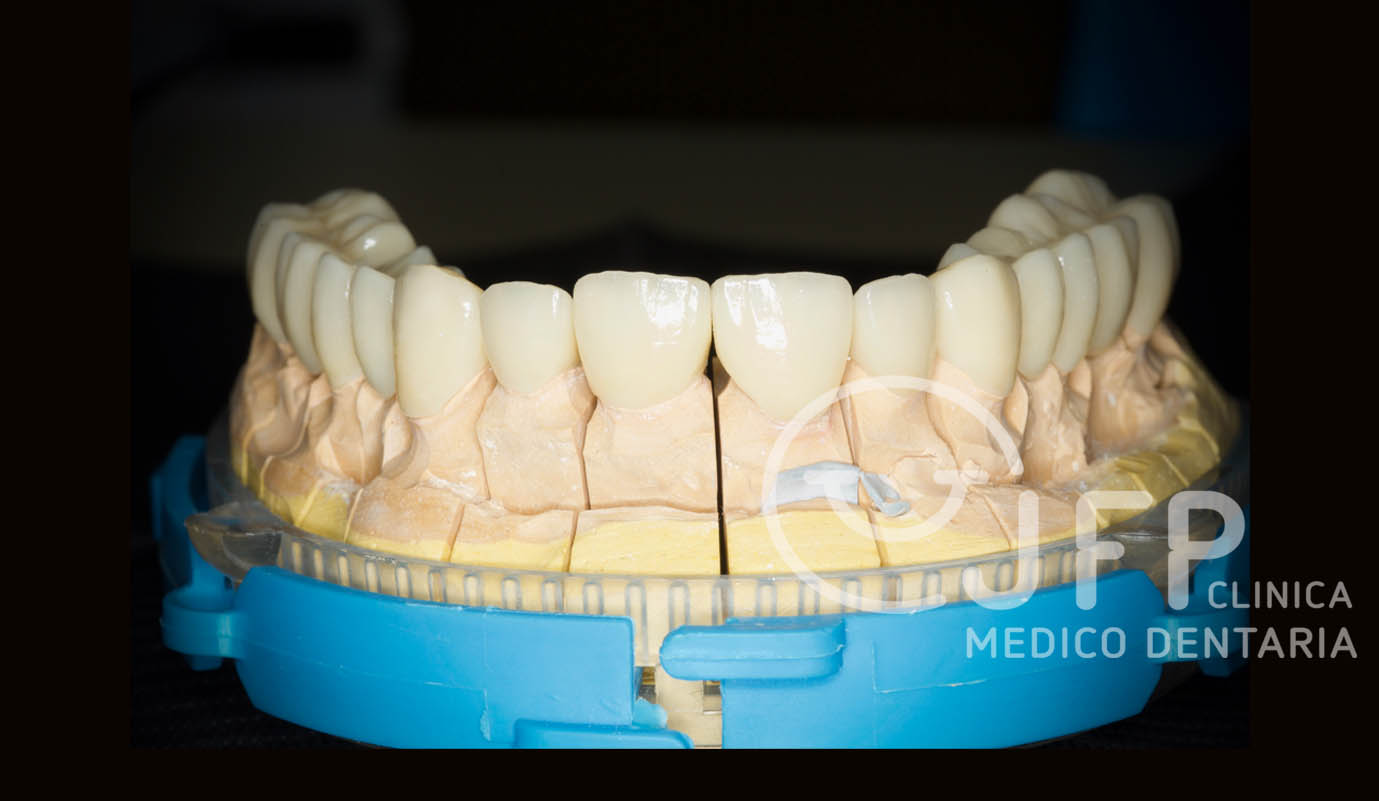

Exemplos em fase laboratorial

Sobre implantes as soluções podem ser para casos unitários ou múltiplos, com estruturas fixas para reabilitar arcadas totais. Estes funcionam como se fossem umas “raízes dentárias artificiais” onde são fixas as coroas cerâmicas. São soluções apetecíveis pelo facto de dar a sensação de ter novamente dentes, mas têm de ser mantidas com cuidado redobrado pois acabam por ser peças artificiais e o que pretendemos é que sejam definitivos sem que haja qualquer tipo de problema posterior.

Casos de próteses sobre implantes